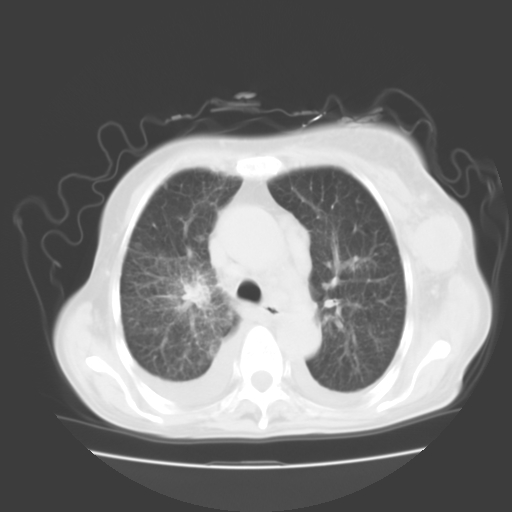

女70y乳腺ca(针吸活检)

多部位转移瘤的诊断可以肯定,我的疑问是:双肺对称高密度影及胸水是否为心衰肺水肿,病人体虚弱,不好意思图象传的乱![em9]

1)左侧乳腺癌并左侧腋窝及纵隔淋巴结转移,两肺淋巴道转移(癌性淋巴管炎),肝脏多发性转移。2)双侧胸腔积液。3)慢性胆囊炎。

3、双肺癌性淋巴管炎;

1)左侧乳腺癌并左侧腋窝及纵隔淋巴结转移,肝脏多发性转移。2)双侧胸腔积液伴双肺蝶翼样磨玻璃高密度影,双侧肺门血管影增粗(图像不全,肺门层面没纵隔窗),考虑心功能不全所致。3)慢性胆囊炎伴壁钙化。